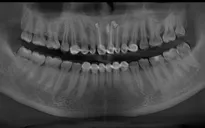

Nghi ngờ đây là một nang xương hàm trên, các bác sĩ cho chụp cắt lớp vi tính hàm mặt. Kết quả là một nang xương hàm trên 2x3cm, có hủy phần xương hàm thông lên mũi. Bệnh nhân được tư vấn phẫu thuật bóc nang và xét nghiệm giải phẫu bệnh.

Khối phồng có hình ảnh dịch vàng bên trong che một nửa đường kính lỗ mũi bệnh nhân. Nghĩ đây là nang mũi má bác sĩ cho chụp CTscan và kết quả đúng như dự đoán. Nang kích thước 1x2cm trên CTscan, nằm vùng mũi má phải.